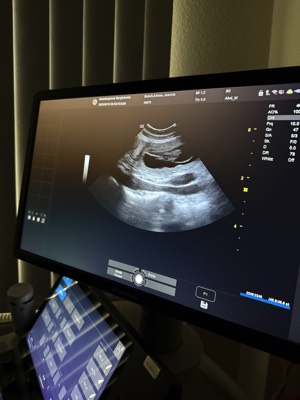

Unsere bezaubernde Jeannie „Tova‘s Riesling Surprise in Germany“ wurde Ende April von unserem charmanten Mio „Golden Nugget's Achilles“ gedeckt.

Wir erhoffen uns von dieser Verpaarung von zwei F3 Windsprites eine Erhöhung der genetischen Diversität mit den damit verbundenen positiven Auswirkungen auf die langfristige Gesundheit der Rasse. Apropos Gesundheit: Jeannie und Mio sind bereits 3,5 und 5,5 Jahre alt. Bis zur Zulassung der F3 Silken Windsprites hat es ja bekanntlich einige Jahre gedauert. Positiv daran ist, dass wir wissen, dass beide Hunde eine phantastische Konstitution und Gesundheit haben. Beide sind körperlich total fit und wirklich robust und unempfindlich – eigentlich waren sie noch nie richtig krank und vertragen jedes Futter.